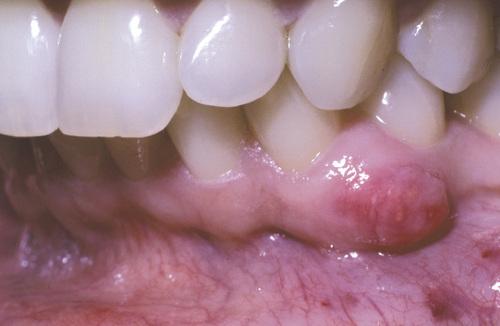

Clinical Features

- soft tissue counterpart of lateral periodontal cyst

- predilection for mandibular canine/premolar area

- found in patients in the fifth and sixth decades

- almost invariably on facial gingiva or alveolar mucosa

- painless, domelike swellings less than 0.5 cm

- often bluish or blue-gray

Tense, fluid-filled swelling on the facial gingiva. Surgical excision revealed superficial “cupping out” of the alveolar bone.

gingival cyst of the adult